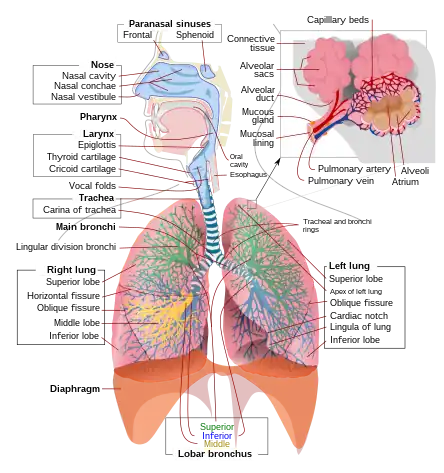

| Respiratory system | |

Respiratory failure results from inadequate gas exchange by the respiratory system, meaning that the arterial oxygen, carbon dioxide, or both cannot be kept at normal levels. A drop in the oxygen carried in the blood is known as hypoxemia; a rise in arterial carbon dioxide levels is called hypercapnia. Respiratory failure is classified as either Type 1 or Type 2, based on whether there is a high carbon dioxide level, and can be acute or chronic. In clinical trials, the definition of respiratory failure usually includes increased respiratory rate, abnormal blood gases (hypoxemia, hypercapnia, or both), and evidence of increased work of breathing. Respiratory failure causes an altered mental status due to ischemia in the brain.

The typical partial pressure reference values are oxygen Pa O

2 more than 80 mmHg (11 kPa) and carbon dioxide Pa CO2 less than 45 mmHg (6.0 kPa).[1]